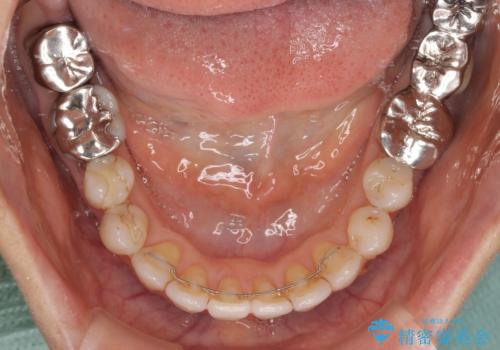

前歯の突出感と上下の隙間 インビザラインによる矯正治療

- 前歯の上下スペースと前歯の隙間を気にして来院された患者様です。

インビザラインにより上下の前歯の隙間を閉じながら、IPRを用いて口元の突出感を合わせて改善していくこととしました。

上下の隙間に舌が入り込むことが、すきっ歯やオープンバイトの原因であったため、舌の筋肉のトレーニングも並行して行い、後戻りの抑制を図りました。